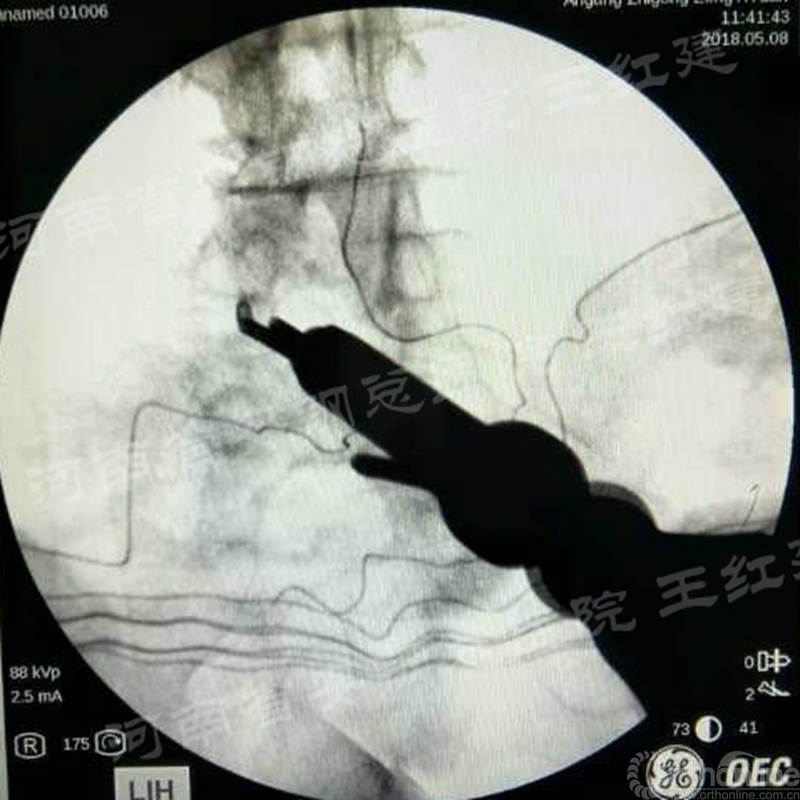

应用通道技术进行植入融合时,首先要更换工作套管,通过枪钳、抓钳的应用处理椎间盘,接着进行自体骨或同种异体骨及cage植入,并通过C臂透视确定试模型号放置融合器,最终完成植骨融合。

镜下观察椎间处理后终板软骨

镜下植骨

确定融合器位置